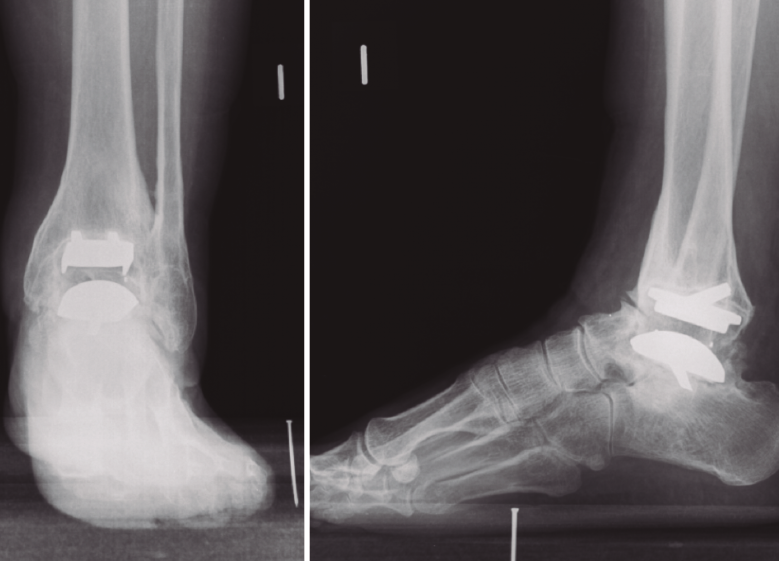

Figura 1. Radiografías preoperatorias. Aflojamiento aséptico de la prótesis Ramsés.

En todos los casos se observaron signos de consolidación radiológica a las 24 semanas (Figuras 1 y 2). El implante de tantalio ha presentado una buena integración sin que se hayan observado signos de osteolisis o colapso en el hueso adyacente, manteniéndose invariable la longitud de la extremidad en todos los casos.